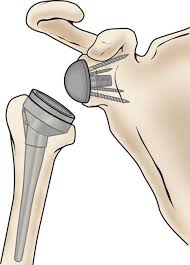

החלפת מפרק כתף הפוכה

החלפת מפרק כתף מלאה